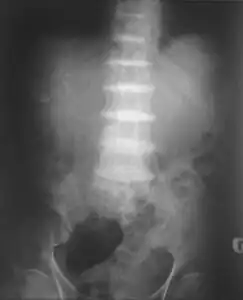

-

Intervertebral discs calcification due to ochronosis]] -